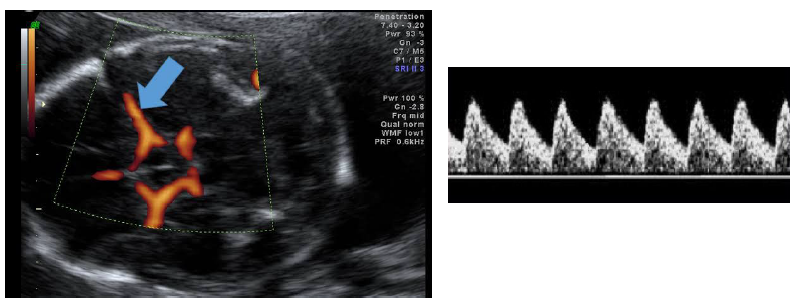

Com base nas imagens, assinale a artéria que está sendo estudada e a conduta esperada.